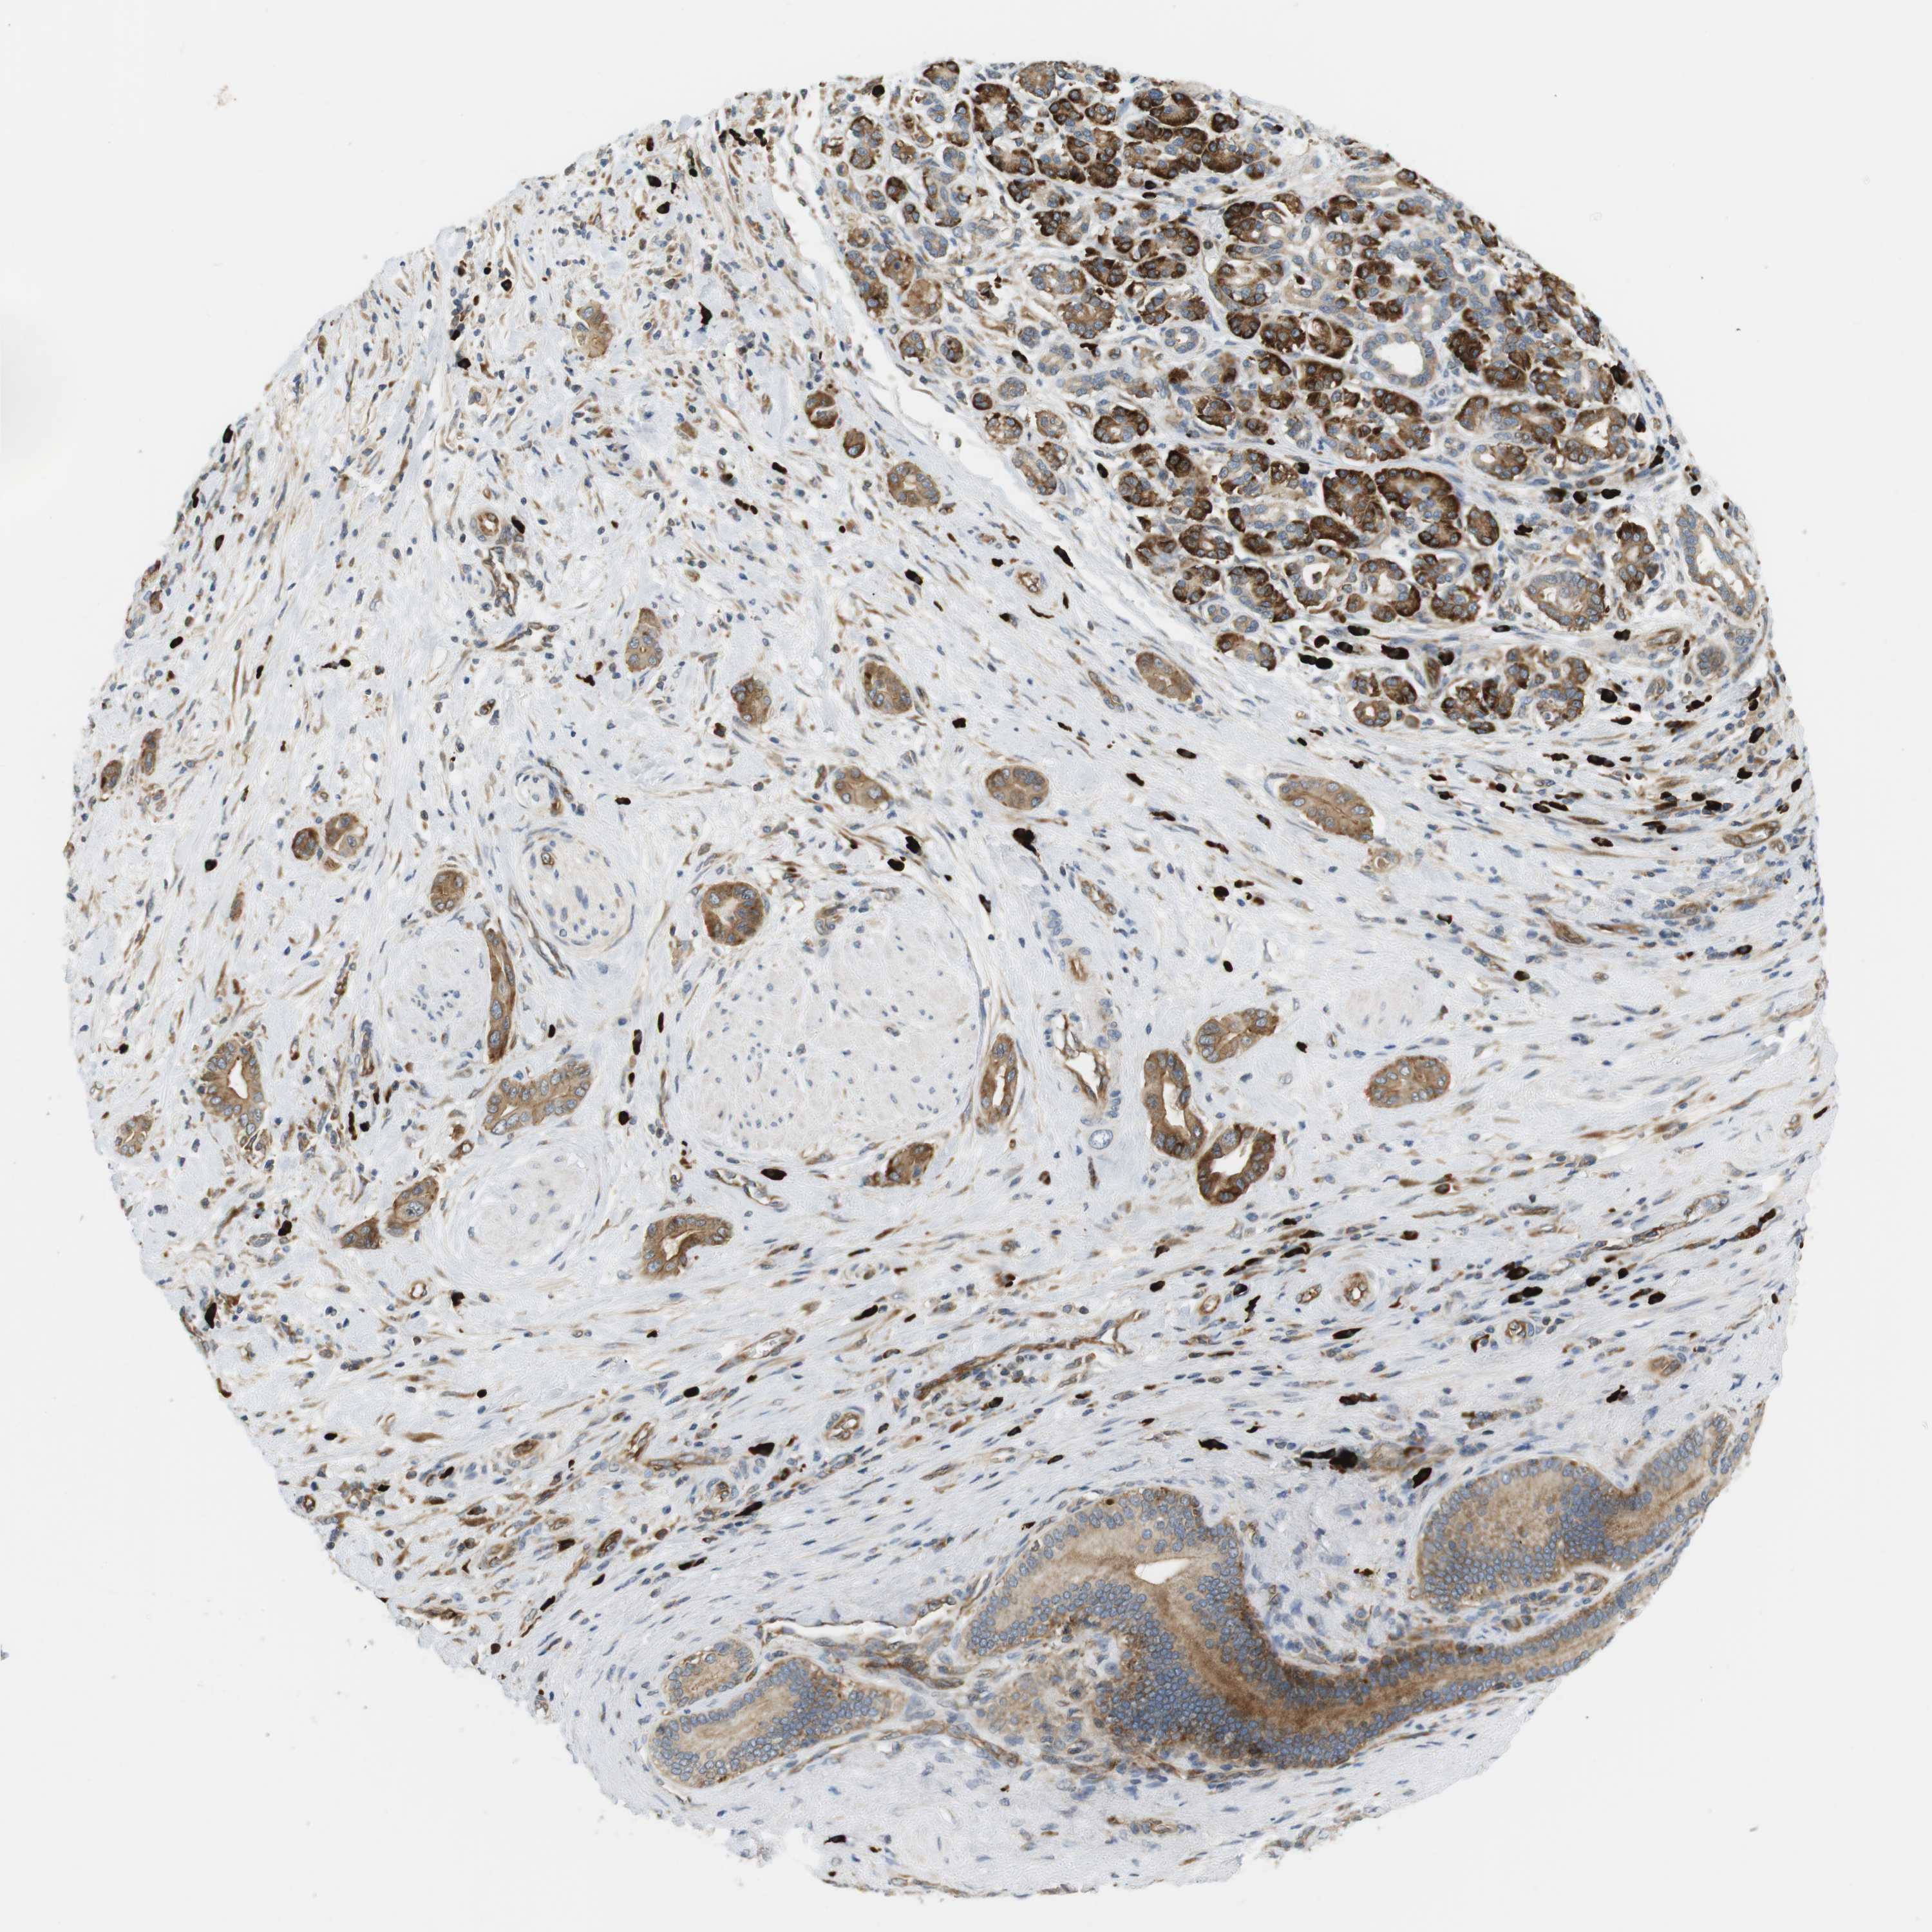

PANCREATIC CANCER - Protein expressioni

A mouse-over function shows sample information and annotation data. Click on an image to view it in a full screen mode. Samples can be filtered based on level of antibody staining by selecting one or several of the following categories: high, medium, low and not detected. The assay and annotation is described here.

Note that samples used for immunohistochemistry by the Human Protein Atlas do not correspond to samples in the TCGA dataset.

Antibody stainingi

Antibody staining in the annotated cell types in the current human tissue is reported as not detected, low, medium, or high, based on conventional immunohistochemistry profiling in selected tissues. This score is based on the combination of the staining intensity and fraction of stained cells.

Each image is clickable and will lead to virtual microscopy that enables deeper exploration of all samples and also displays staining intensity scores, fraction scores and subcellular localization as well as patient and tissue information for each sample.

Antibody HPA014396

Staining

High

Medium

Low

Not detected

Intensity

Strong

Moderate

Weak

Negative

Quantity

>75%

75%-25%

<25%

None

Location

Nuclear

Cytoplasmic/membranous

Cytoplasmic/membranous,nuclear

Adenocarcinoma, NOS